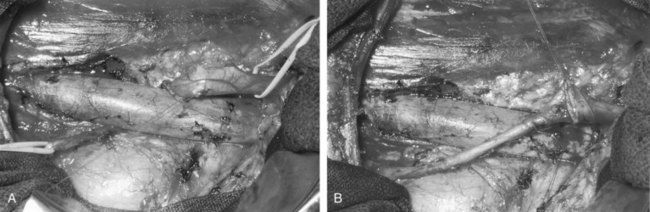

The initial retroperitoneoscopic approach to pyeloplasty was first reported by Janetschek and colleagues (1996). Cystoscopy with retrograde pyelography and ureteral stent placement are first performed as described earlier. For the retroperitoneal approach, the patient is usually positioned in the flank position with the use of flexion and elevation of the kidney rest. Following Hassan access technique to enter the retroperitoneum, a retroperitoneal working space can be created with balloon dilation. Following CO2 pneumoretroperitoneum, three to four laparoscopic ports are used to perform the laparoscopic pyeloplasty. The ureter is usually identified early in the procedure, and the dissection, mobilization, and ureteropelvic junction repair steps are identical to those described for the transperitoneal approach (Fig. 41–14).

Figure 41–14 A, Retroperitoneal laparoscopic photograph of a case with right ureteropelvic junction (UPJ) obstruction. Note the presence of a lower pole crossing renal vessel anterior to the UPJ. B, Intraoperative view of completed ureteropelvic anastomosis after retroperitoneal laparoscopic dismembered pyeloplasty.